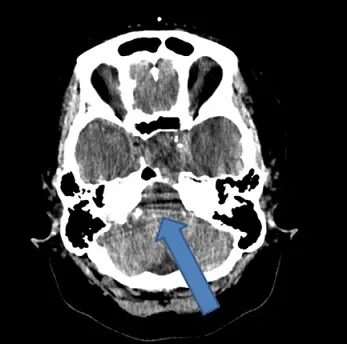

下圖腦部電腦斷層攝影影像中,箭號所指的假影最主要是下列何種因素造成的?

影像為腦部軸位(axial)CT 平掃,截面位於後顱窩(posterior fossa)層面,可見小腦(cerebellum)、岩骨(petrous bone)等結構。藍色箭號所指處為一條跨越後顱窩、呈現深色條紋狀(dark streak/band)的假影,走向大致橫跨兩側岩骨之間的腦實質。該假影輪廓較模糊、非完整環形,位於高密度骨骼結構之間——這是射束硬化假影最典型的空間分布特徵:出現在兩個高衰減(high-attenuation)結構(此例為兩側岩骨)之間的路徑上。

影像中未見模糊的移動邊界(可排除移動假影),未見以旋轉中心為圓心的環形亮暗帶(可排除環狀假影),亦未見偵檢器失靈常見的單一環狀條紋(可排除偵檢器故障假影)。